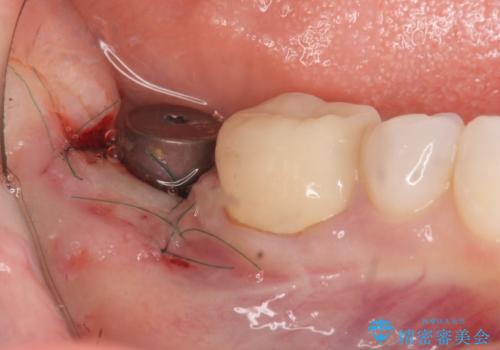

骨との結合する期間が早く、大きな咬合力にもしっかりと耐えることのできるストローマンインプラントを用いた咬合機能回復を計画します。

- 外科手術のため、術後に痛みや腫れ、違和感を伴います